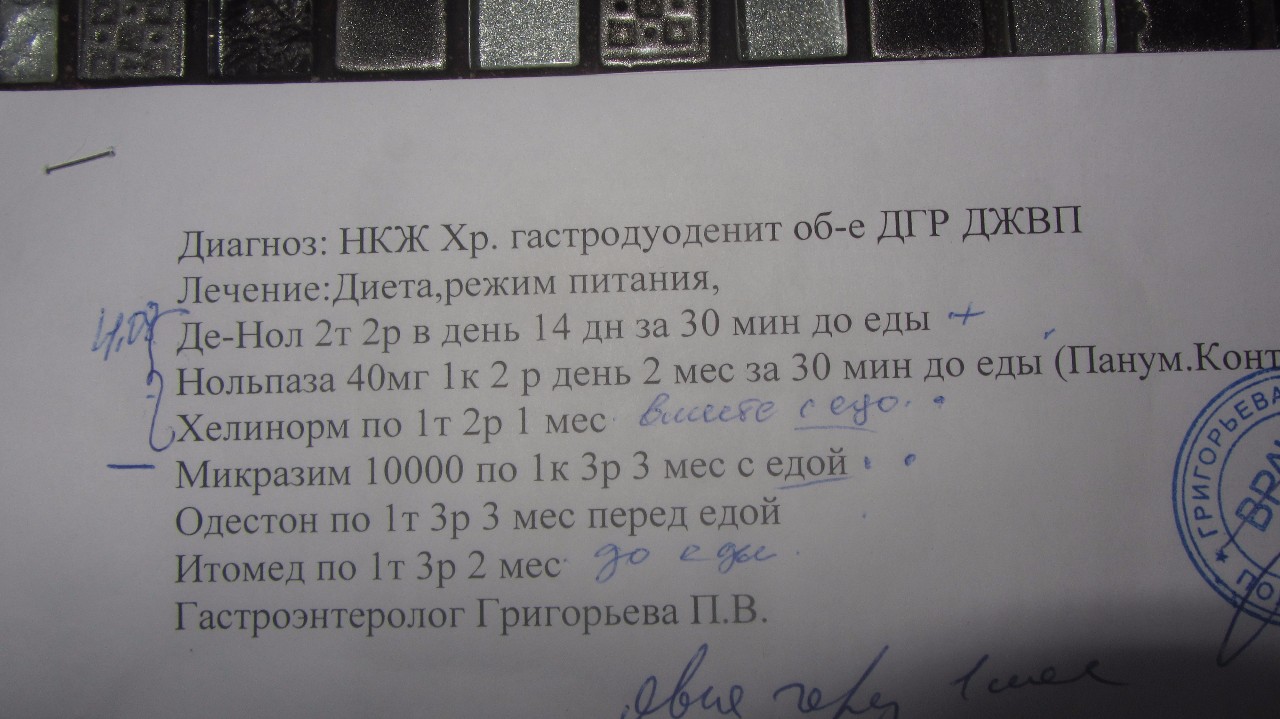

Информация и фотографии о хроническом гастрите и дуодените